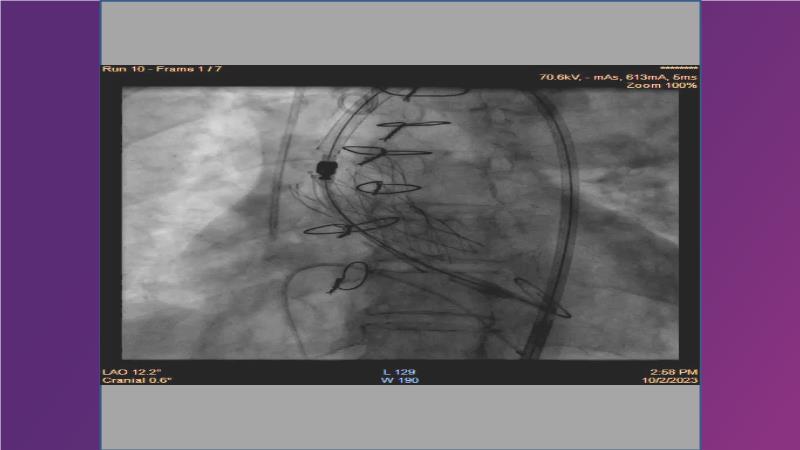

Gain expertise in selecting the appropriate TAVI device for achieving stable deployment in a 90-degree horizontal aorta. Discover techniques for ensuring smooth deliverability, particularly when navigating through tight and tortuous anatomies. Additionally, learn strategies to prepare for future coronary access, irrespective of the height of the left or right coronaries.

• To witness smooth deliverabilty even crossing tight and tortous anatomy